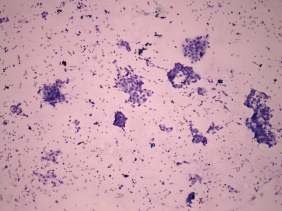

Cytology was performed from the discrete lesion in the left lobe and resulted in Hashimoto's thyroiditis.

Our final diagnosis was hypothyroidism caused by Hashimoto's thyroiditis. A benign lesion in the left lobe.

Histopathology disclosed Hashimoto's thyroiditis without any nodule.